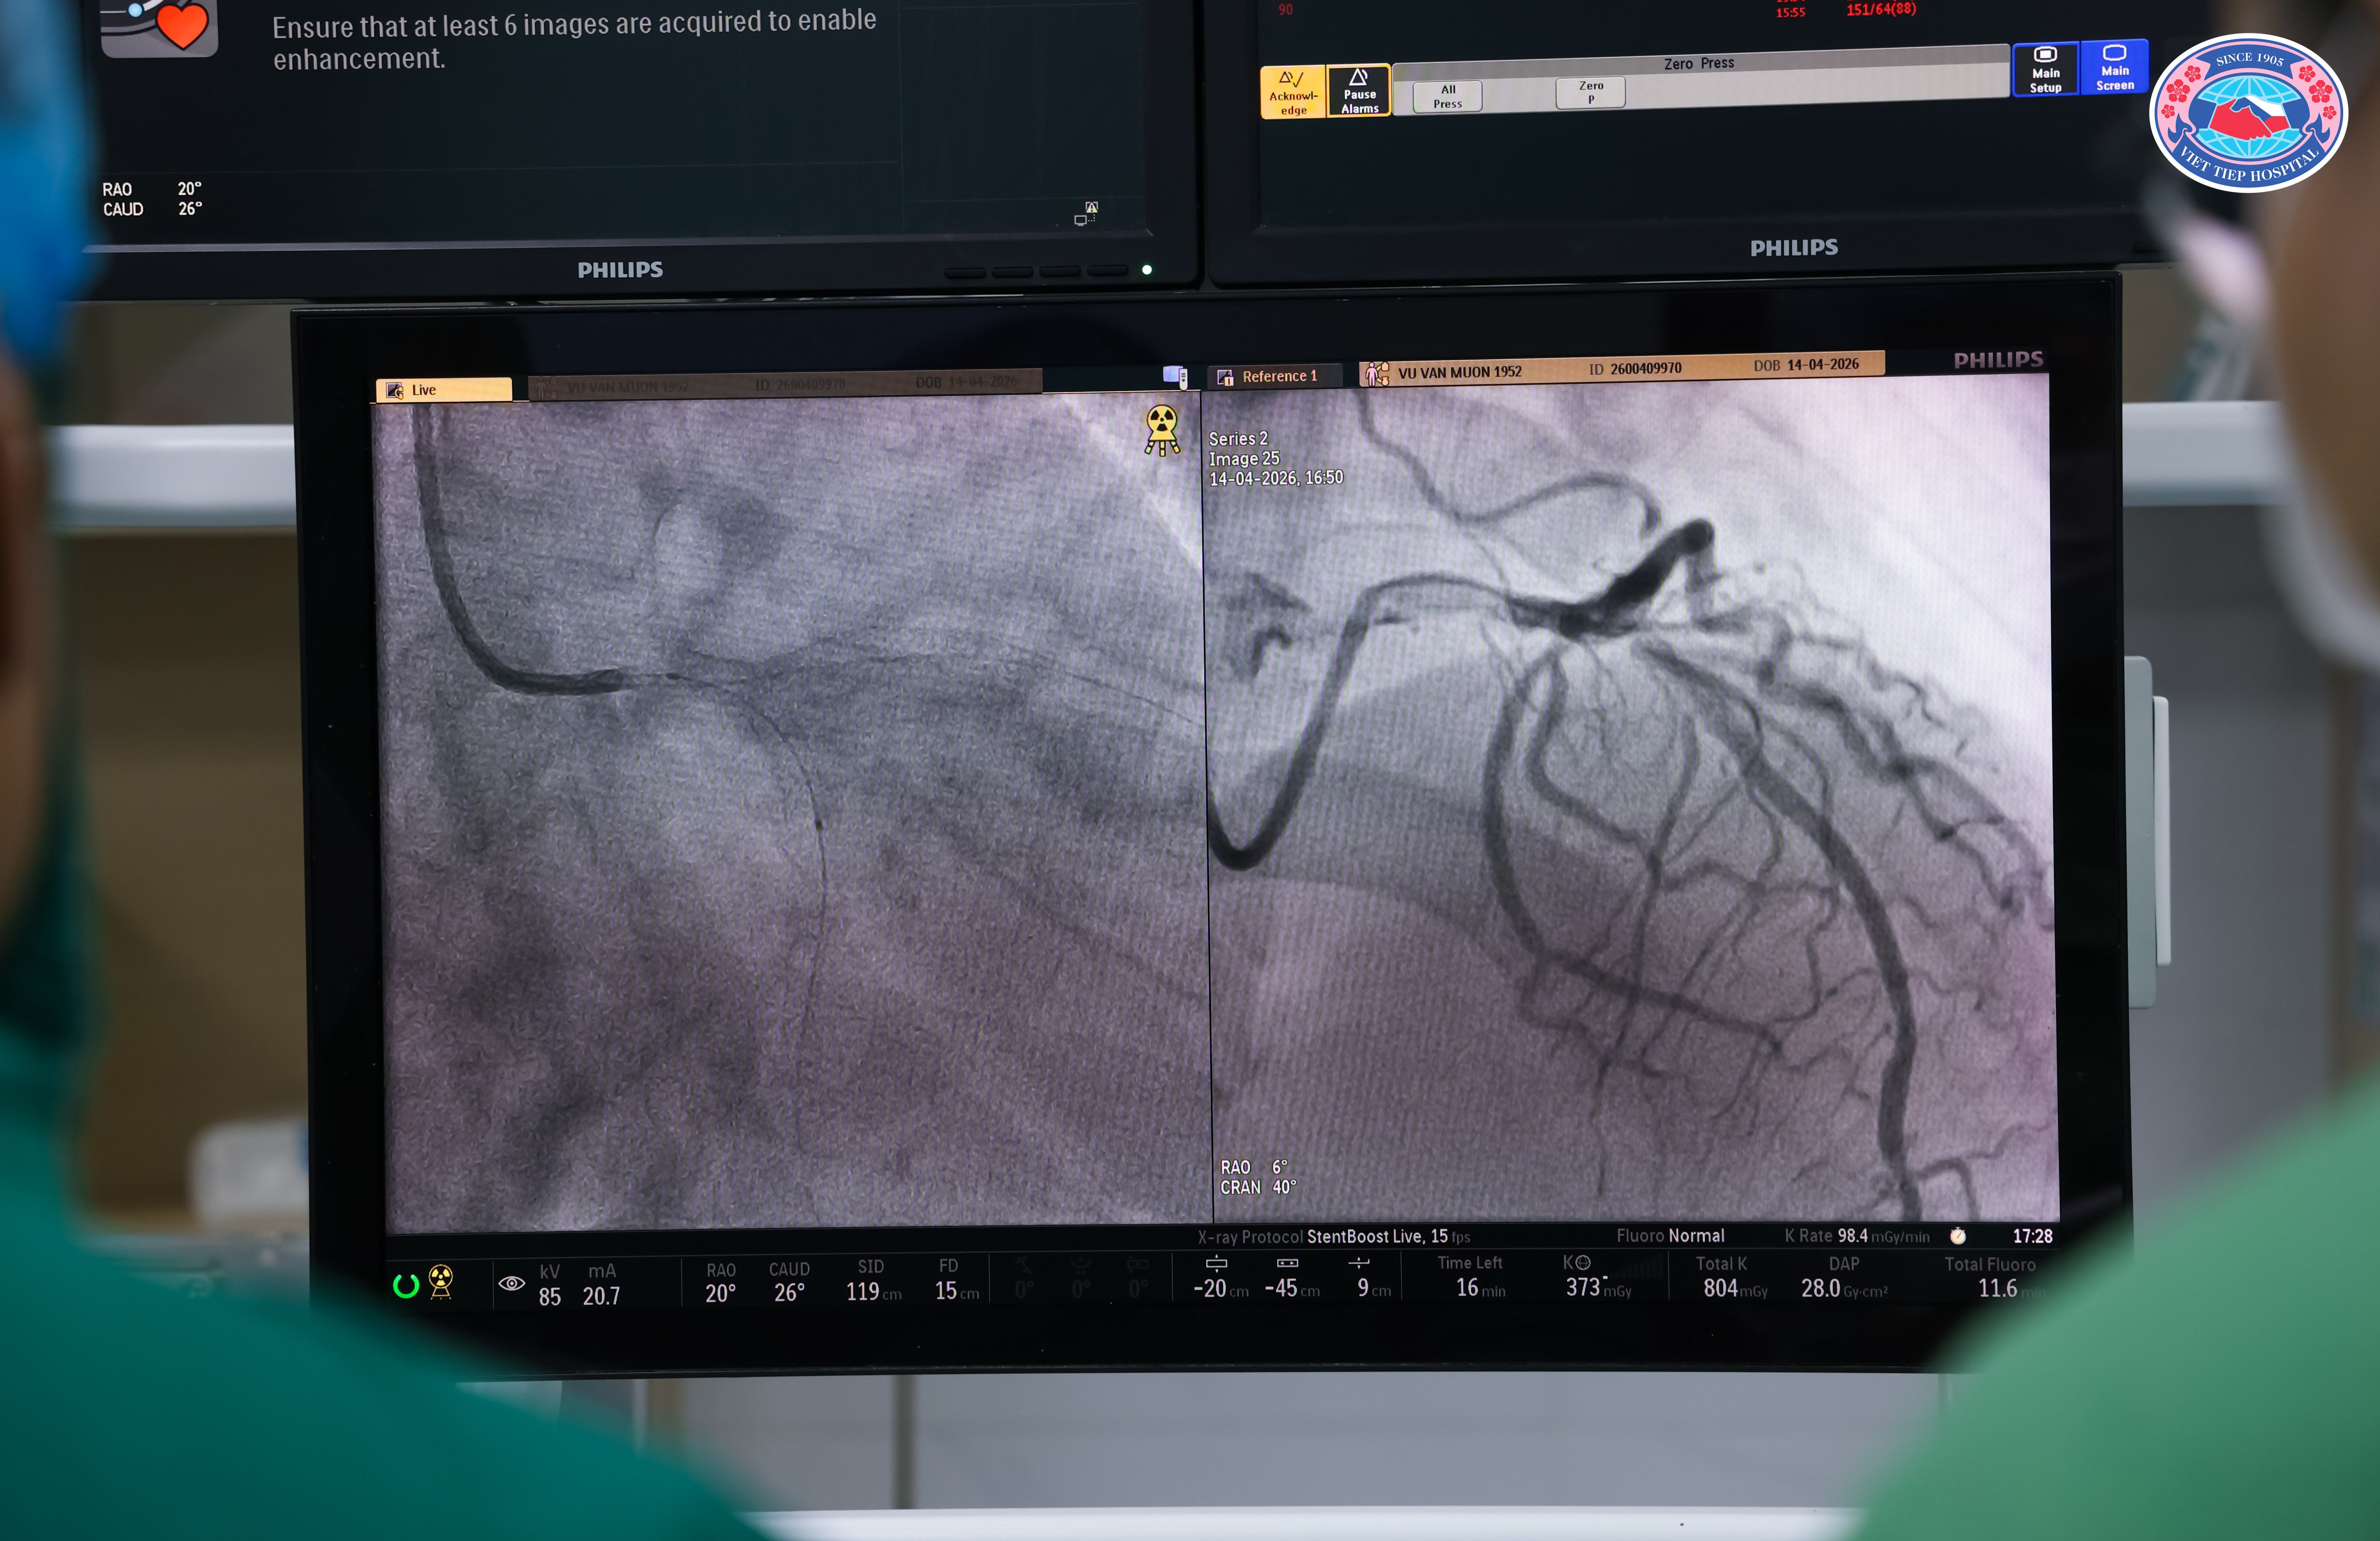

Siêu âm trong lòng mạch (IVUS) được ví như “đôi mắt thứ hai” của bác sĩ can thiệp. Khác với chụp mạch thông thường chỉ cho hình ảnh gián tiếp, IVUS sử dụng đầu dò siêu âm đưa vào trong lòng mạch để tái tạo hình ảnh cắt lớp chi tiết của thành mạch và lòng mạch. Nhờ đó, bác sĩ có thể đánh giá chính xác đặc điểm mảng xơ vữa, mức độ hẹp, kích thước lòng mạch, cũng như hỗ trợ lựa chọn kích thước và tối ưu hóa việc triển khai stent. Nói một cách dễ hiểu, IVUS giúp bác sĩ không chỉ “thấy” mà còn “hiểu” rõ hơn tình trạng của người bệnh.

Nội dung chương trình tập trung vào vai trò của IVUS trong can thiệp mạch vành, hướng dẫn sử dụng và phân tích hình ảnh, kết hợp thị phạm các ca bệnh thực tế cùng chuyên gia giàu kinh nghiệm. Những trao đổi sát với thực tiễn lâm sàng đã giúp người tham dự dễ hiểu, dễ áp dụng trong công việc.

(Các chuyên gia trực tiếp thị phạm kỹ thuật, thực hiện ca can thiệp ứng dụng IVUS trên người bệnh thực tế tại Bệnh viện Hữu Nghị Việt Tiệp)